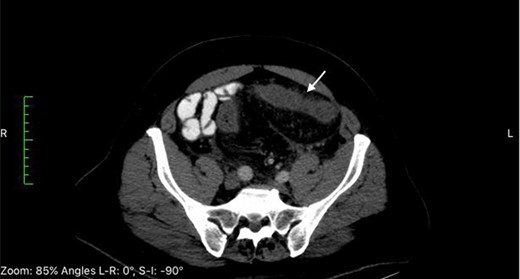

Repeat computed tomography of the abdomen 12 days after admission reveals progressive thickening of the sigmoid colon [long white arrow] and free fluid [short white arrow].

A 63-year-old Middle-Eastern man developed sudden onset of lower abdominal pain and non-bloody diarrhea. At time of presentation there was no report of fever, chills, nausea or emesis. The patient was overall healthy except for a history of benign prostatic hyperplasia and degenerative osteoarthritis of the knees, which he treated for several months with a Chinese herbal supplementation. The past surgical history was significant for tonsillectomy and inguinal hernia repair. The patient had received a course of oral ciprofloxacin due to worsening of his diarrhea. He was admitted to the hospital and laboratory results were significant for an elevated C-reactive protein at 140 mg/L. Computed tomography (CT) scan revealed left sided colitis involving the sigmoid and descending colon (Fig. 1). Serosal irregularity and pericolic inflammation change with mesocolic vascular congestion and hyperemia. Colonoscopy showed edema and erythema without gross ulceration. An additional course of intravenous ciprofloxacin and metronidazole was unsuccessful in resolving the symptoms leading to the administration of ertapenem and azithromycin by the treating gastroenterologist. Subsequent stool studies were positive for Entamoeba histolytica prompting a full course of oral tinidazole. With worsening of the patient’s symptoms, a second CT scan performed 12 days later demonstrated interval progression of the colitis to the distal transverse colon with free intra-abdominal fluids (Fig. 2). Repeat colonoscopy to assess for inflammatory bowel disease showed diffuse edema and erythema without deep ulceration. Biopsies revealed non-specific severe colitis. Despite bowel rest with total parenteral nutrition and the various intravenous and oral antibiotics, the patient continued to deteriorate prompting an extended left hemicolectomy with end transverse colostomy and a low Hartmann’s rectal pouch 26 days after initial presentation. Examination of the 75 cm specimen revealed macroscopic features of ischemia with indurated brown-reddish bowel wall and bulky hardened mesenteric fat tissue (Fig. 3). Gross inspection of the inflamed mucosa revealed a fibrinous layer. Histopathologic assessment showed inflammation and fibrosis of the mucosa, especially of the lamina propria with rarefaction of the crypts. Proliferation of small vessels was visible in the lamina propria, the submucosa and the pericolic fat. Moreover, some vessels showed a fibromyxoid wall-thickening. Elastic van Gieson (EvG) stains revealed massive changes in venous structures with hyperplasia of the cellular and matrical mass in the initmal layer leading to subtotal occlusion of the venous lumens. Histology identified focal secondary thrombosis. Some lymph nodes were rich of plasma cells with a dilated sinus with ectasia of the lymph vessels. The findings were consistent with IMHMV.